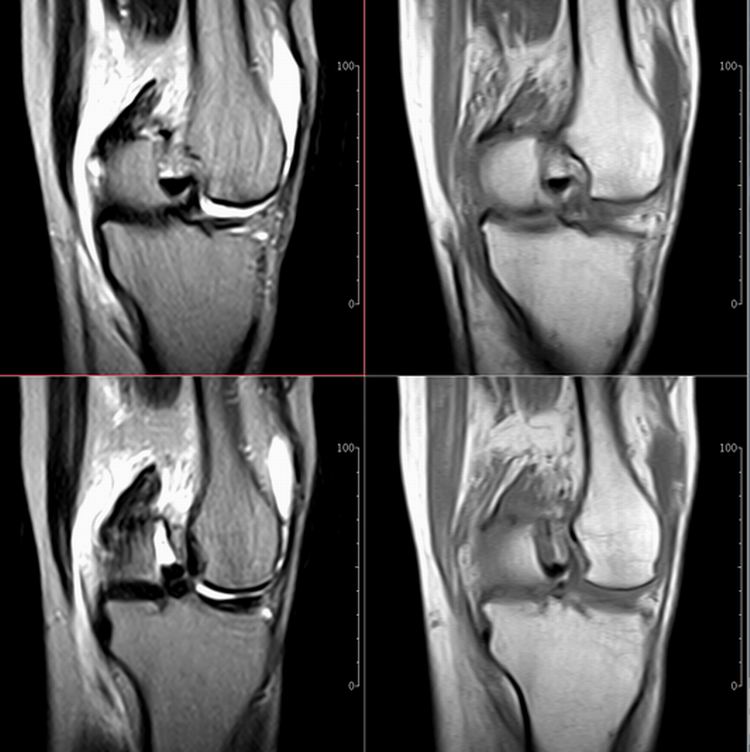

标题: MRI1910:M 687Y。近日因外伤疼痛,而就诊。

m 687y。近日因外伤疼痛,而就诊。有外侧副韧带损伤吗??因片子较差各位请包涵。

关节退行性变伴股骨外髁关节面下囊肿,不除外剥脱性骨软骨炎.关节积液,髌骨软化症

体位不标准。关节退变伴关节积液。

1)膝关节骨质退行性改变。

2)由于体位的关系不能确定有外侧副韧带的损伤。

关节退变伴关节积液,外侧副韧带的损伤

关节积液,外侧副韧带的损伤